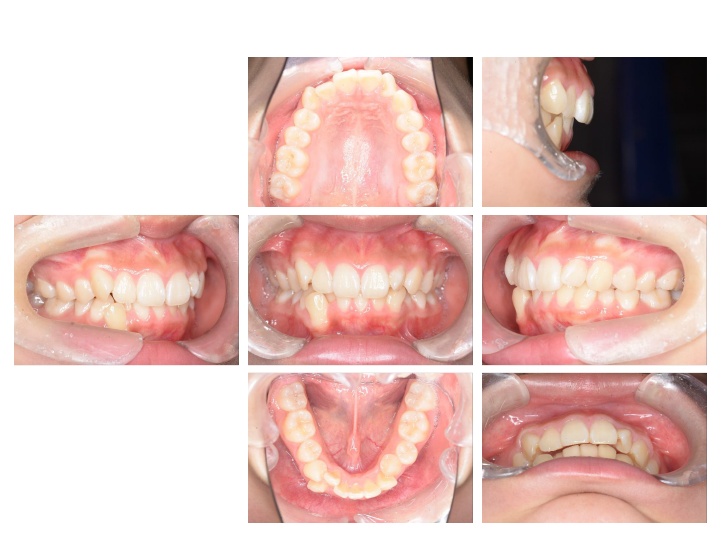

3.お顔が綺麗になる

口腔周囲筋にもアプローチし、お顔の骨格自体を整えることができるため顔貌も変わります。

骨格にアプローチする矯正治療で無闇に歯を抜いたりせず、自然と正しい位置に歯が並ぶよう、一人一人に合わせた確実な治療を行います。